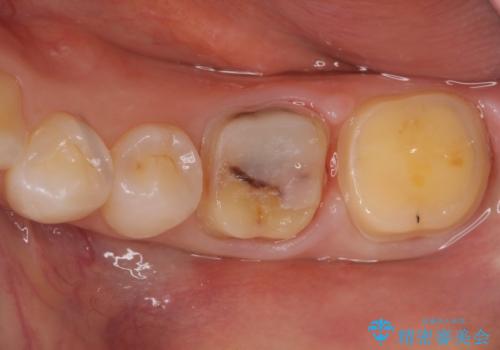

変色した樹脂の詰め物 セラミックでのやり替え

奥歯が樹脂の詰め物で継ぎ接ぎになっていることが確認されたため、今後の虫歯リスクを減らすために適合の良いフルジルコニアクラウンを入れていきます。

樹脂で継ぎ接ぎになった歯はそうでない歯と比べて虫歯になるリスクが高いです。

樹脂をすべて取り、虫歯も取り切った後に適合の良いクラウンを装着することで今後の虫歯リスクを減らすことができます。